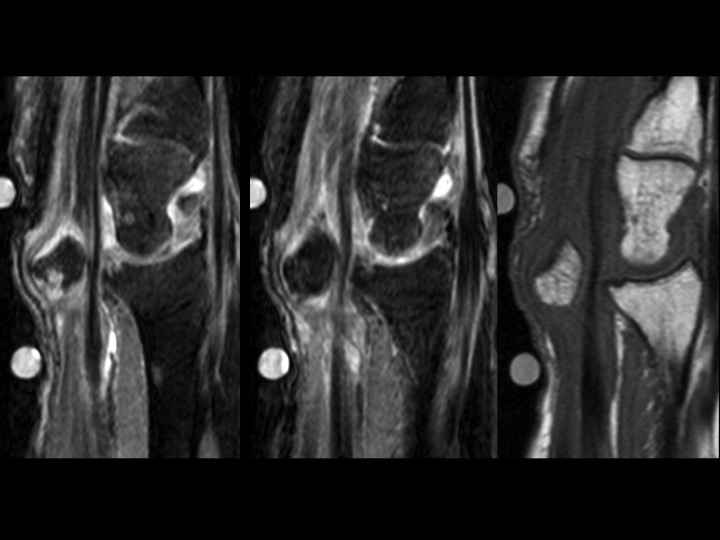

53F 6-8 mos pain with mass in carpal tunnel

What makes this amusing (to me) is that the radiographs (slide 5) were done and reported (by me) 4 days prior to MRI. Patient claims prior work related injury, though this was not the focus of the office visit note. The hand surgeon interpreted the XR in his note as no scapholunate interval widening, no DISI (thats the funny part). MRI was ordered to evaluate mass in the carpal tunnel region. The patient moved a little because she was in alot of pain. The Sag PDFS images show the median nerve being stretched and compressed anterior to the chronically dislocated lunate. (the lunate seems to be happy) Reference article.

Lunate dislocation